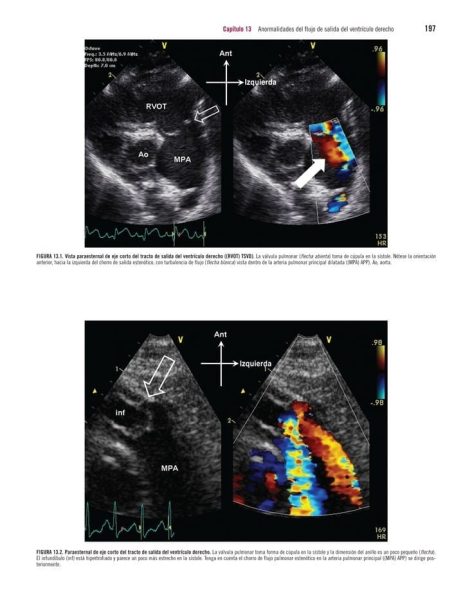

Capítulo 10.- Válvula Pulmonar en Salud y en Enfermedad